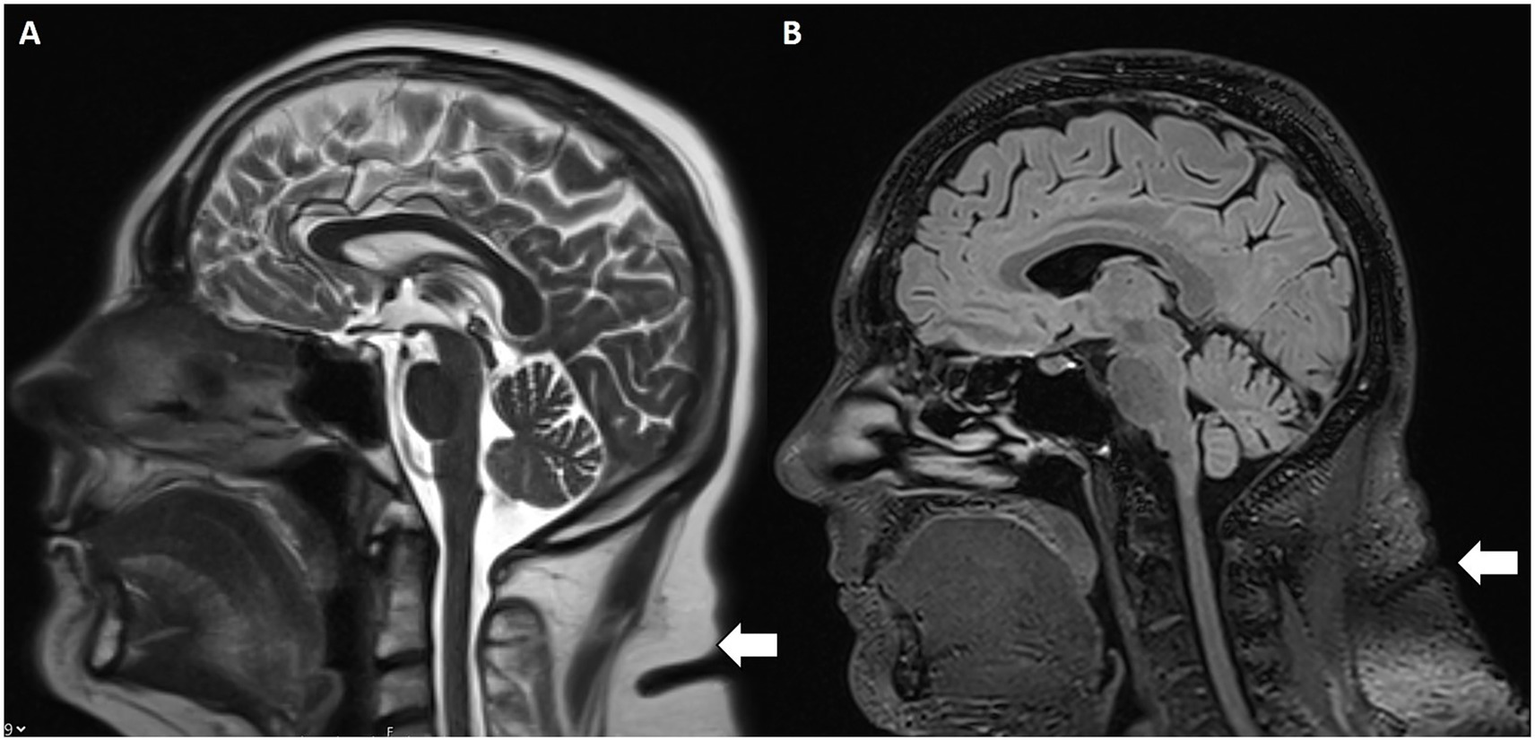

Increased subcutaneous fat thickness in the scalp and neck were evaluated as further IIH MR findings (22). Specifically, patients with IIH demonstrated significantly greater scalp fat thickness at the level of the coronal suture and increased neck fat thickness at the C2–C3 vertebral body interspace (Figure 6) compared to controls with incidental empty sella turcica. These findings support subcutaneous fat thickness as a potential imaging marker associated with intracranial hypertension.

Figure 6

Increased subcutaneous nuchal fat. Sagittal T2w (A) and FLAIR (B) MRI with increased subcutaneous fat (white arrow) at the C2–C3 intervertebral disc space.